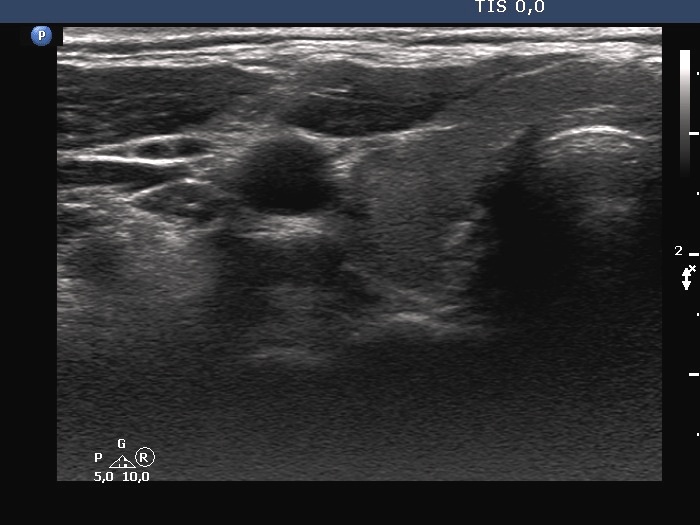

Second examination a year later (second row of images):

Ultrasonography. The thyroid has significantly decreased in size. The echogenicity became normal. The left lobe has already had discrete hypoechoic lesions but the size of them was much smaller compared with the previous visit.

3. if we had any doubts about the diagnosis after the first examination, it disappeared after the second visit: the size of the lobes decreased, the echogenicity became normal and although the discrete lesion has been already present, it also decreased in size.